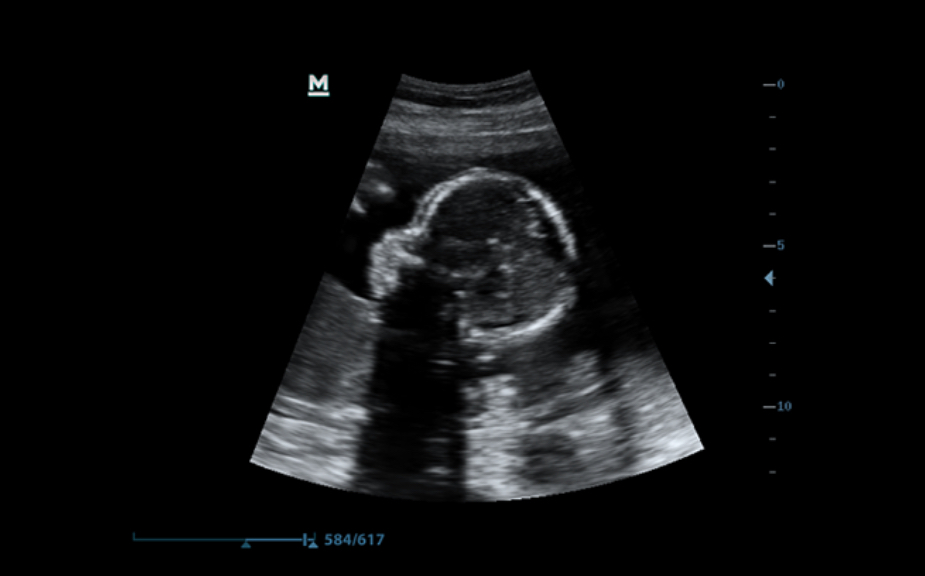

Three-dimensional/four-dimensional photography

Including 3D/4D Flip & Sync features that provide quick and easy viewing of image size from any orientation

ILife

By integrating the Ray-sending algorithm with a new virtual lighting pattern, the iLive app generates a stunningly realistic view of the fetus with images resembling human skin.

The Smart face

The new Z50 device provides quick and intelligent one-touch fetal face enhancement. It can instantly remove any blockages in the sound data, get rid of unwanted noise information, and provide an optimal view of the fetus's face with minimal effort.